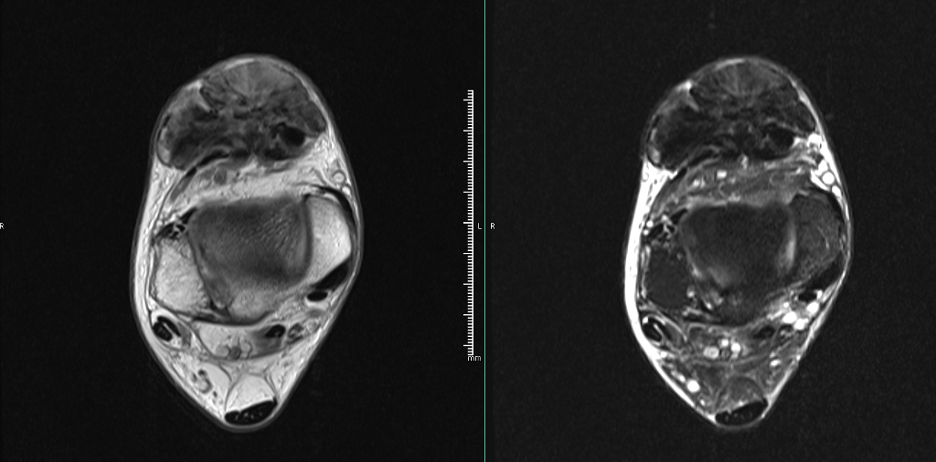

The patient received a referral to our clinic for consideration of soft tissue mass excision. An MRI revealed a 6.0 x 5.8 x 3.1 cm mass at the anterior ankle in close relation to the tibialis anterior and extensor hallucis longus tendons. The soft tissue mass was predominantly hypointense on T1- and T2-weighted images with no postcontrast enhancement (Figures 3-4).

Advanced imaging studies are beneficial when differentiating FTS from other soft tissue masses. MRI findings typically include a hypointense, well-defined lesion on T1- and T2-weighted images.6 The soft tissue mass in our case was similar to previously described FTS, with hypointensity on both T1- and T2-weighted images and no postcontrast enhancement. Our findings are similar to those of Ciatti and colleagues7 who described hypointensity on T1- and T2-weighted images for a mass at the anterior ankle capsule.